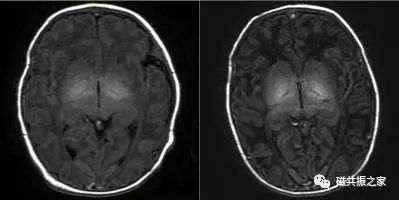

患儿4d,T2WI FSE△,1.5T。

左:TR=3100ms,TE=120ms。

右:TR=5200ms,TE=210ms。

对于婴幼儿颅脑的扫描,特别是对于小于3个月的婴儿,不管是T1WI还是T2WI,都应适当的延长TE和TR值,以获得更好的图像信噪比和对比度,且扫描参数应根据磁场及扫描目的做出相应的调整。婴幼儿随着年龄的增长TR逐渐降低,通常至2周岁时与成人TR类似。